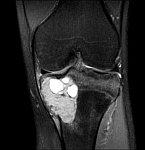

- Resection of benign and malignant tumors of the bone and soft tissue

- Reconstruction of bone defects by biological procedures (from spongiosaplasty to bone transfer)

- Tumor total endoprosthesis (TEP) of all large joints and bones